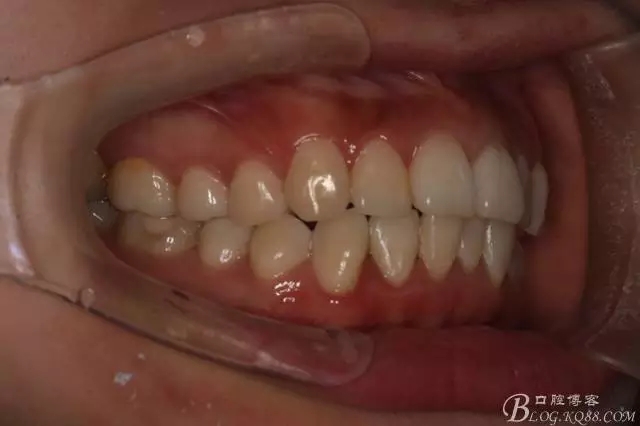

患者,女,主訴:牙齒不齊。

如圖,該病例為簡單排齊病例,但77鎖合是矯治中的關鍵所在,你會怎么處理?

該病例主要為17、27頰側(cè)位同時伴有伸長,當然種植支抗可以解決,但還有簡單實用的辦法嗎?如圖,在橫腭桿遠中延伸出牽引鉤,位置盡量遠離合平面,7粘舌側(cè)扣,牽引力的方向為壓低及舌向,下圖為兩個月的效果,17已到位,27還未到位。